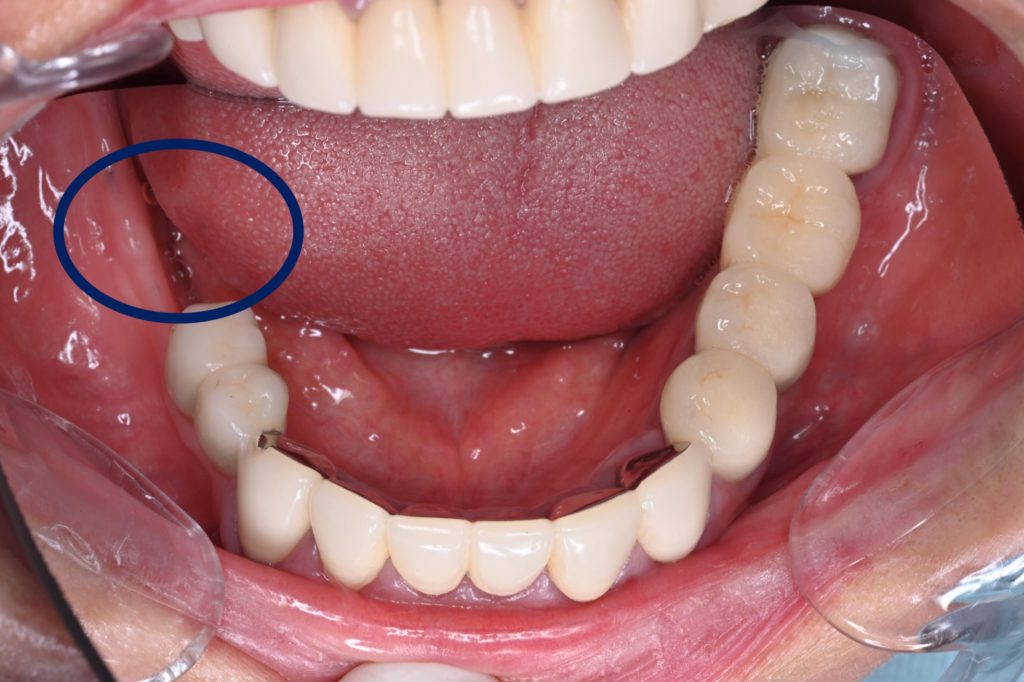

ボトムアップトリートメントから顎運動診断の元トップダウントリートメントに切り替えた症例(GBR,インプラント、CADIAX、デジタル、全てのセラミックのやりかえ希望)

| 主訴 | 右下にインプラントを入れたい |

| 診断名 | 臼歯部欠損および全顎的咬合崩壊 |

| 年齢・性別 | 47歳 女性 |

| 治療期間・回数 | 30ヶ月 |

| 治療方法 | 当初は他院でインプラトができたいと言われた部分(右下)の骨造成処置後インプラト埋入手術を行なった。元々全てセラミックが入っていたが、全体的なバランス(咬合平面、咬合高径)、や歯の色に改善の余地があったため、患者との話し合いの上、可撤性のマウスピースでのトライ→接着性のトライ→セラミックへの置き換えを行なった(デジタルにて)。CADIAXにて術前、術中での顎運動の評価も行なった。 |

| 費用 | 3,230,000円 |

| 注意点 | 外科手術に伴う腫脹・疼痛・出血、インプラント周囲炎のリスク、補綴物の破損リスク |